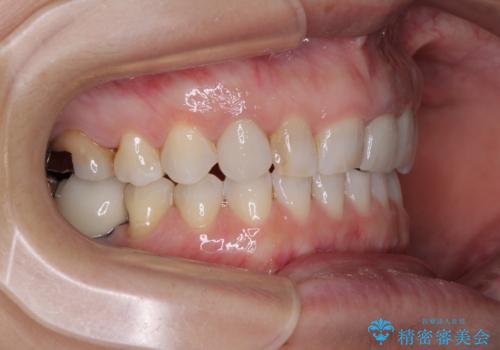

- 右下の奥歯が痛く、全体的に咬み合わせがおかしい気がするとのことで来院された患者様です。

診察したところ、上顎前歯に過剰歯があることで上顎歯列が大きくなり、上下の歯が奥歯の一部でしか咬み合っていない状態でした。

そのため右下の奥歯に強い負担が生じていて、むし歯が大きかったこともあり、抜歯が必要な状態でした。